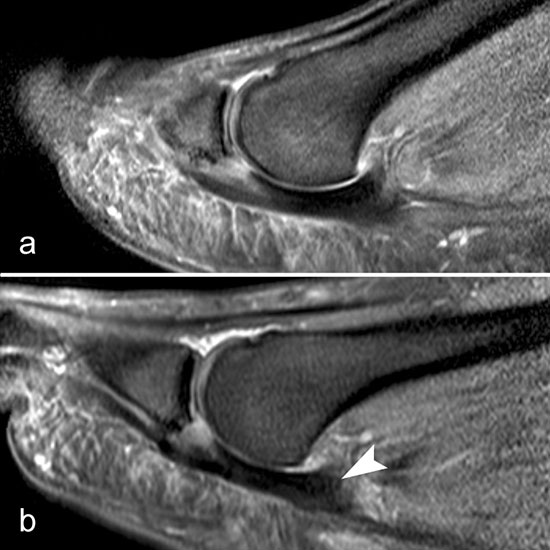

Ein Sonderfall stellt die Großzehe dar: Hier verstärken die Sesambeine, das intersesamoidale und die sesamophalangealen Bänder die Gelenkkapsel. Der faserknorpelige Anteil der plantaren Platte distal der Sesambeine ist oft nur sehr dünn. Verletzungen dieser plantaren Kapselstrukturen des Großzehengrundgelenkes werden auch als „turf toe“ bezeichnet

(Abb. 8).

Die sagittalen PD FS Schichten im medialen und lateralen Bereich der plantaren Platte (a, c) zeigen eine völlig unauffällige,  Der kleine Flüssigkeitseinschluss in der Mittellinie der Zehe (b, Pfeil) entspricht einem physiolo

Zwischen der plantaren Platte und der Grundphalanx ist in der Mittellinie des Gelenkes ein kleiner Rezessus vorhanden (Abb. 9).

Dieser flüssigkeitsgefüllte Raum darf nicht als Ruptur der plantaren Platte fehlinterpretiert werden 23. Verletzungen der plantaren Platte erfassen immer auch den medialen oder lateralen Zügel.